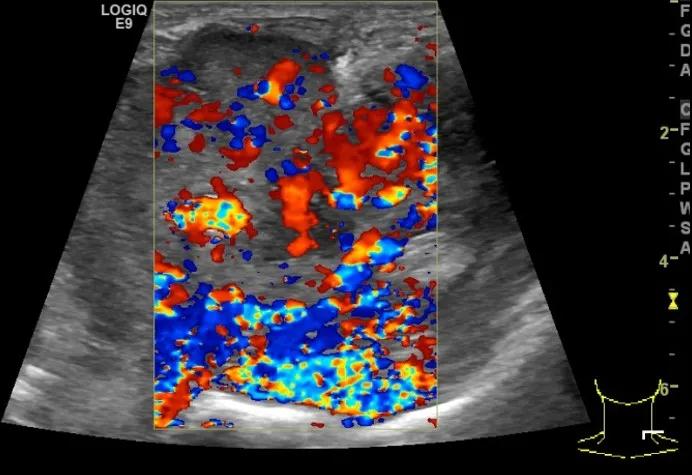

第四例是胸腺癌化妆包,术后、化疗之后淋巴结转移,肿块范围巨大,99mm*61mm,边界不清,呈浸润状,肿块包绕颈动脉,颈内静脉压闭,症状明显。由于患者放化疗也不敏感、血供非常丰富,于是采取多点姑息性消融。姑息性消融后未实现完全消融,病灶大片坏死,肿胀疼痛得到明显的缓解,后续患者未再来复查。

(病例4图例)